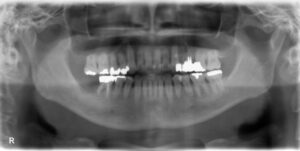

上下7本欠損症例

BEFORE AFTER 74歳男性/上下7本欠損/インプラント埋込手術 【治療内容】 下顎は義歯を使用されていましたが…